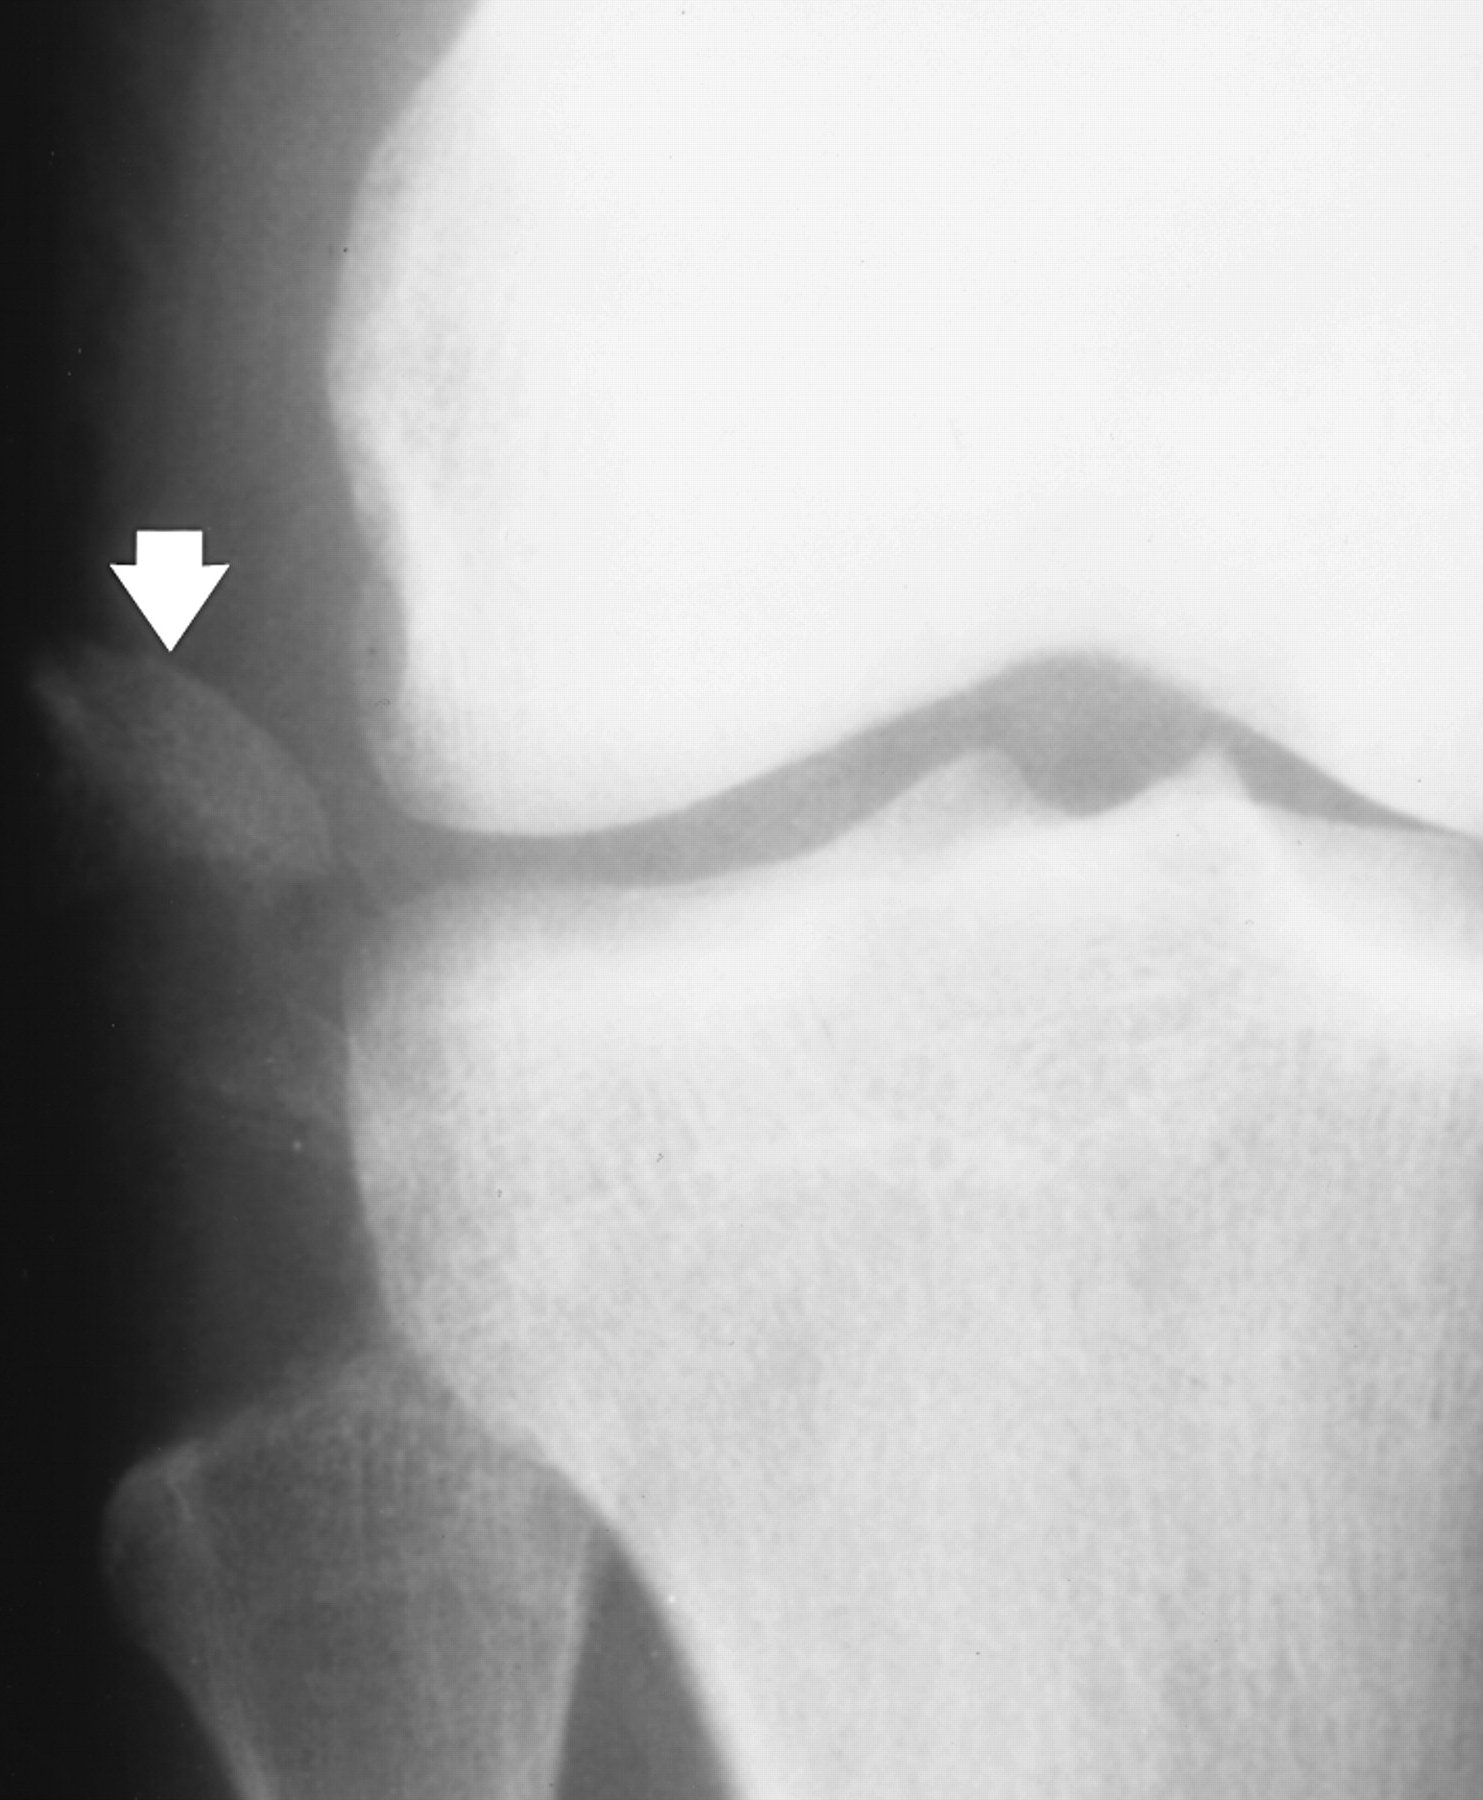

XRAYS |

AP and Lateral views

Avulsion fractures are common and easily missed. This may involve the lateral epicondyle, a Segond capsular avulsion or occasionally there is a tell tale avulsion of the tip of the fibular head indicating distraction of the lateral ligaments, this is termed the "Arcuate sign".